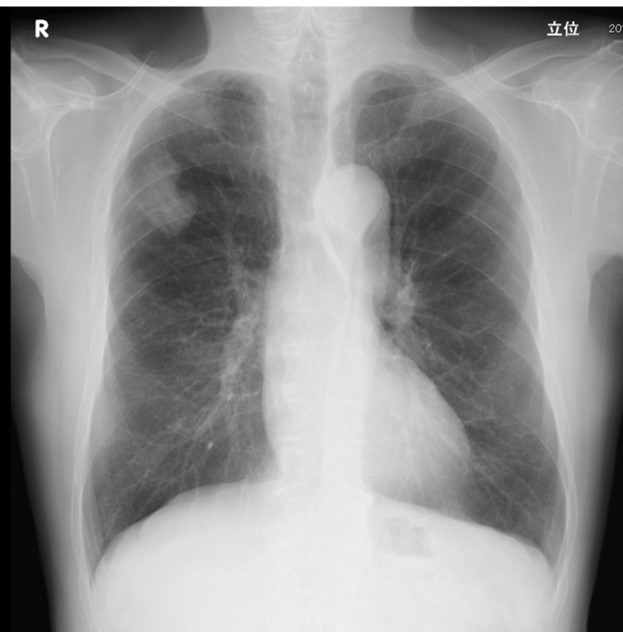

開院以来、肺癌手術の95%が胸腔鏡を使用して行われています。もっとも多い術式は胸腔鏡下肺区域切除術です。また気管支形成術や血管形成術などの難しい手技が必要な場合でも胸腔鏡による手術が行われています。当科ではCT画像を基に術前に肺動静脈や気管支の立体画像を作成して、手術方法の検討や手術のシミュレーション、術中ナビゲーションに活用し、安全確実に手術を行うように努めています。